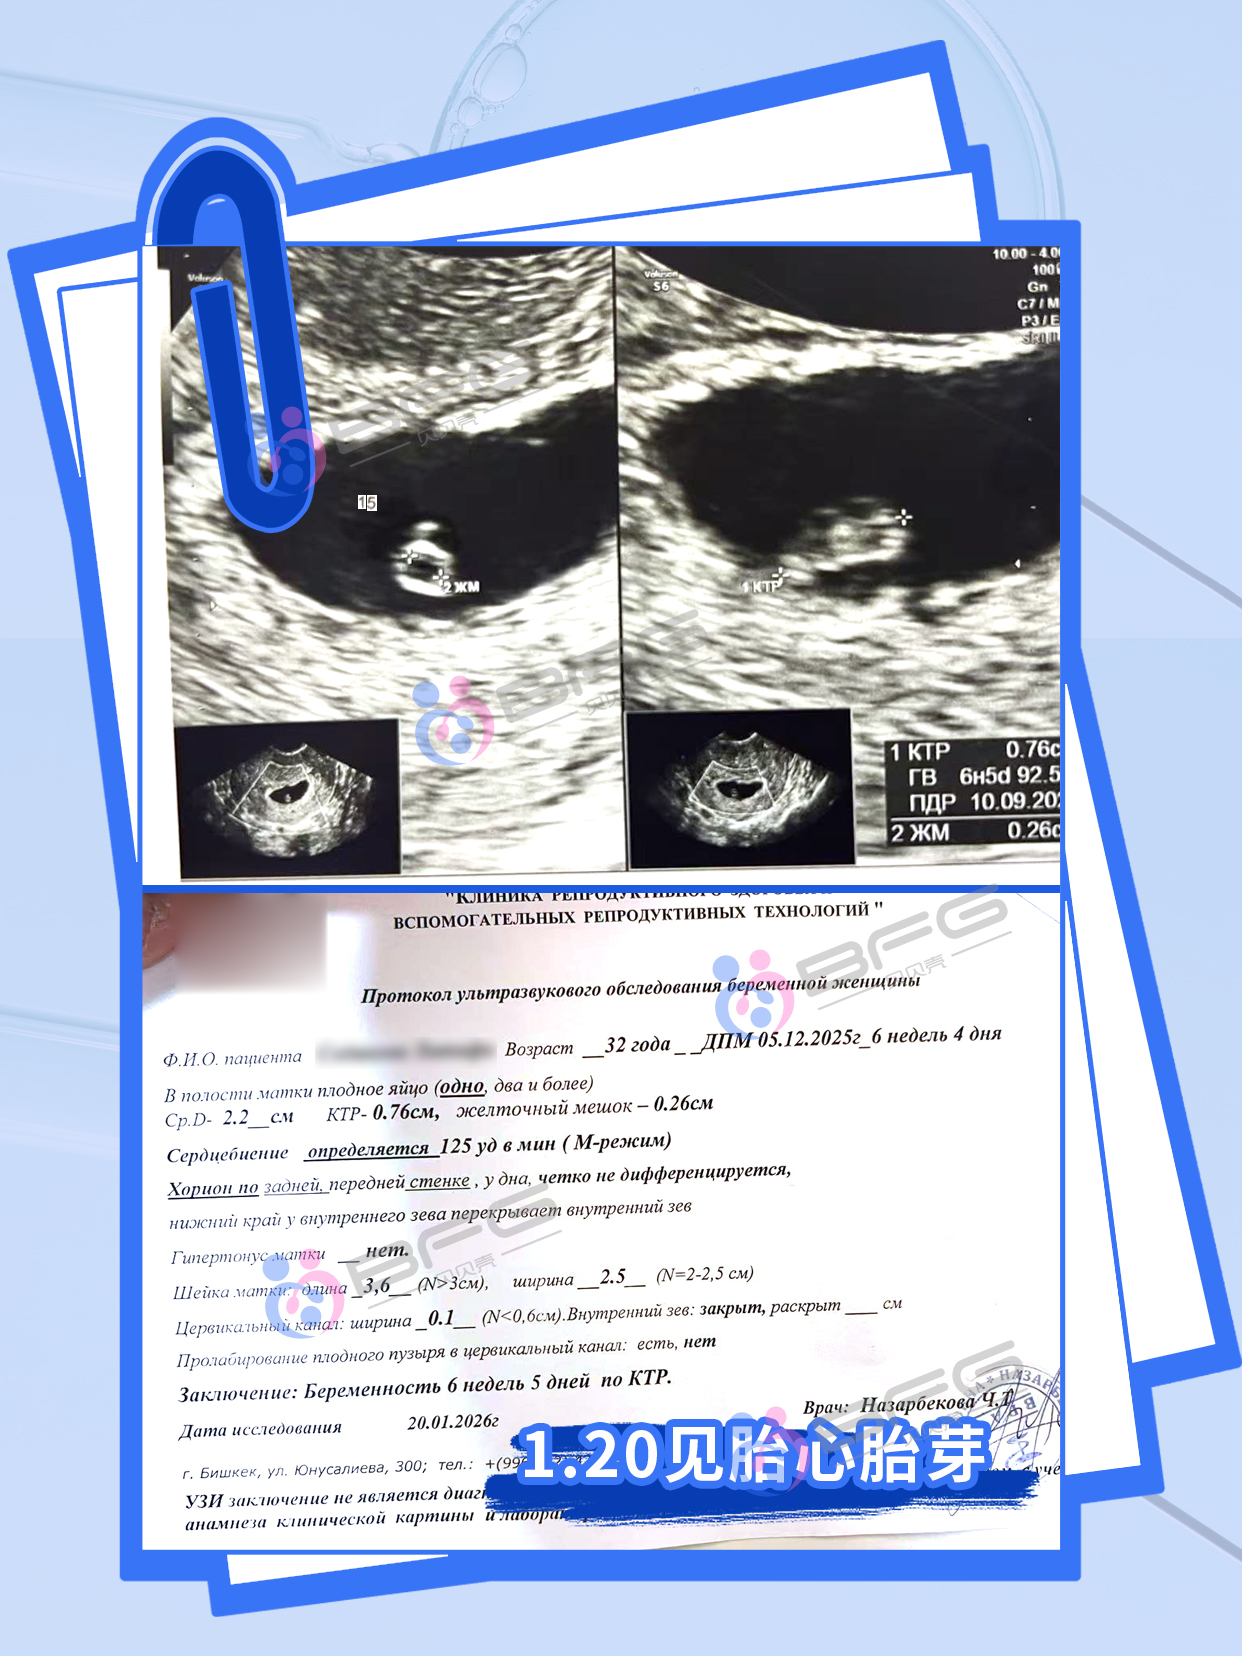

❤妈妈胎心胎芽已出,砰砰的心跳声,带来又一个家庭的圆满!BFG陪伴您抱娃的每一步,让每个家庭都拥有新生的欢笑~